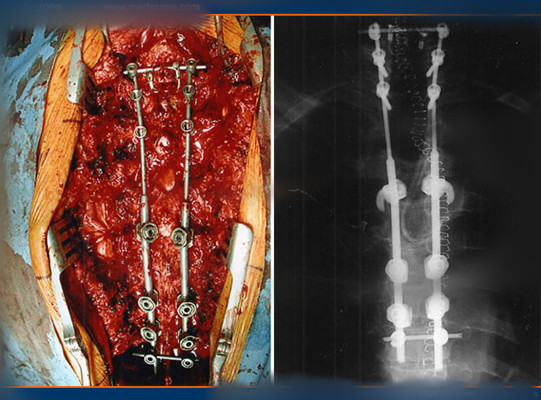

顱內血腫圖片

硬膜下血腫 (30)

硬膜下血腫 (31)